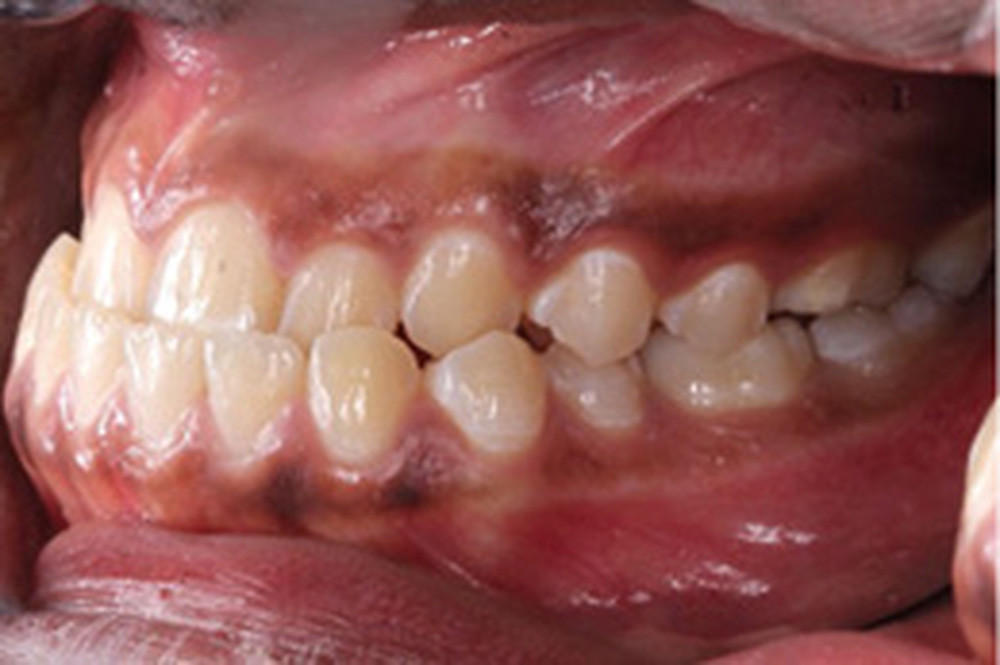

L’examen clinique endo-buccal révèle une denture adulte jeune avec un inversé d’articulé antérieur de 13 à 23, des tatouages gingivaux ethniques et des taches de décalcifications, un parodonte sain mais un brossage insuffisant.

L’arcade maxillaire est en V et la voûte palatine profonde. L’arcade mandibulaire a une forme en U (non-concordance des formes d’arcade) et présente des malpositions des dents cuspidées. La médiane mandibulaire est décalée à gauche de 2 mm ; le recouvrement antérieur est de 2 mm ; les molaires sont en classe III avec un surplomb inversé.